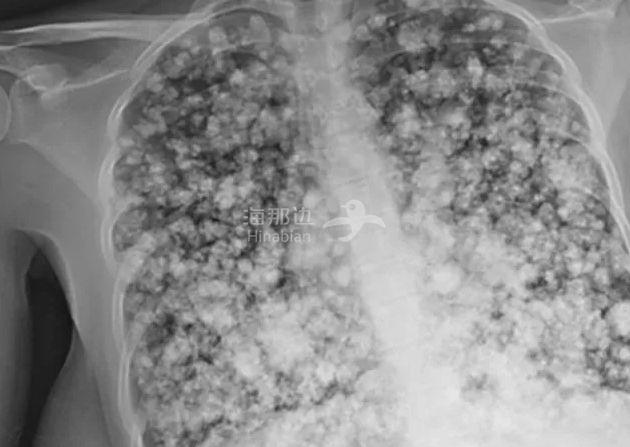

被送往医院检查后,医生发现,他的肺部已经破损严重,新闻里用了一句形容词:Popcorn Lung爆米花肺部...从拍摄的X光片中同样可以清晰的看到这一点。

他的整个肺部全都是炎症形成的斑点,这些斑点的存在阻碍了他的呼吸功能,也让肺部失去了净化功能。想要勉强恢复基本的呼吸,他必须接受器官移植,也就是更换肺部,还没等他的父母感到庆幸,医生又追加了一句,因为他的病情严重,免疫系统已经遭到破坏,即使更换了肺部,他最多也只能延长6年的生命。